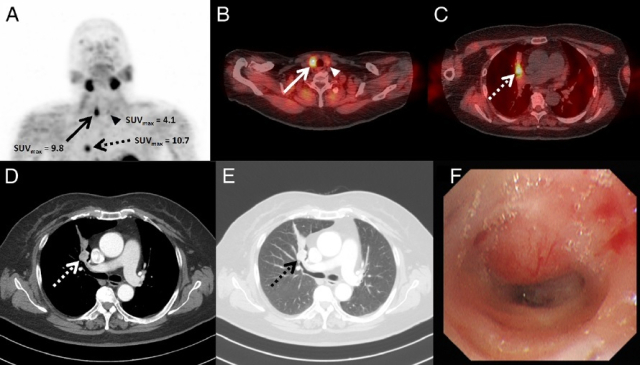

99mTc-MIBI SPECT/CT 결과. 동남권원자력의학원 제공 99mTc-MIBI SPECT/CT 결과. 동남권원자력의학원 제공

논문에 보고한 사례는 원발성 부갑상선 기능항진증이 의심되는 71세 여성 갑상선암 환자에게 부갑상선 99mTc-MIBI SPECT/CT를 시행한 결과, 부갑상선 선종 이외에 이미 진단된 갑상선암과 당시에 알지 못했던 폐의 병소가 관찰되어 폐암 가능성이 보고됐고, 조직 검사를 통해 소세포 폐암으로 확진됐다. 과거 SPECT/CT를 이용해 두 가지 서로 다른 종양을 발견한 사례는 보고된 바 있으나, 세 가지 종양을 동시에 발견한 경우는 극히 드물다.

이 환자에게 99mTc-MIBI SPECT/CT와 18F-FDG PET/CT 검사를 시행했을 때 소세포 폐암에서 최대 표준화섭취계수가 각각 10.7, 3.0으로 나타나 99mTc-MIBI SPECT/CT가 더 높게 측정됐다. 이는 18F-FDG PET/CT에서 잘 보이지 않는 악성종양의 진단에서 99mTc-MIBI SPECT/CT의 보완적 유용성을 보여준다.